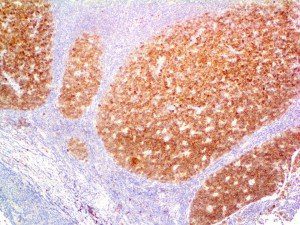

It is the ICU physician who is most likely to witness one of the deadliest manifestations of the abnormal immunological response, the cytokine storm syndrome (CSS). This response is also referred to by some as the cytokine release syndrome (CRS). CSS is characterized by continuous activation and expansion of macrophage and lymphocyte populations, which secrete large amounts of cytokines, causing the cytokine storm. This massive cytokine release is akin to hemophagocytic lymphohistiocytosis (HLH) disease, a syndrome characterized by initial unchecked and persistent activation of cytotoxic T lymphocytes and NK cells.

Clinical and laboratory manifestations of HLH include fever, enlarged liver and/or spleen, neurologic dysfunction, coagulopathy, liver dysfunction, cytopenias (i.e., low levels of erythrocytes, leukocytes, and/or platelets), hypertriglyceridemia, hyperferritinemia, hemophagocytosis, and eventually diminished NK cell activity as the immune system becomes progressively paralyzed. HLH can be familial (primary HLH) or secondary to another disease process (sHLH), such as rheumatic disease, in which it is referred to as macrophage activation syndrome (MAS, characterized by elevated ferritin).